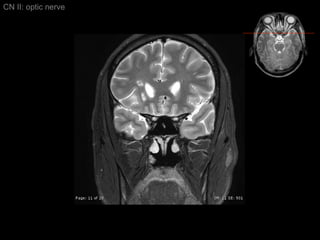

Intraocular segment 1 mm in length Ganglion cell axons exit globe CN II: optic nerve

Intraorbital segment 20-30 mm in length Extended posteromedially from back of globe to orbital apex (within intraconal space) CN2 longer than actual distance form optic chiasm to globe    allowing for eye movement CN II: optic nerve

Intraorbital segment Covered by 3 meningeal layers as brain  Subarachonoid space contains CSF    continue with suprasellar cistern CN II: optic nerve

Intracanalicular Segment Segment within bony optic canal  4-9 mm in length CN II: optic nerve

Intracanalicular Segment CN II: optic nerve Dura of CN2 fuses with orbital periosteum (Periorbita)

Intracranial Segment About 10 mm length from optic canal to chiasm Covered by pia and surrounded by CSF within suprasellar cistern CN II: optic nerve